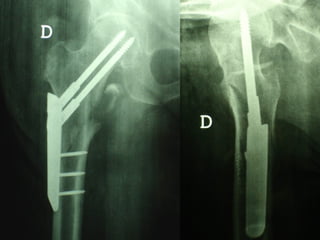

La placca a compressione percutanea (PC.C.P.) di Gotfried è un mezzo di sintesi studiato per assicurare un “impattamento controllato” delle fratture pertrocanteriche grazie alle due viti telescopiche prossimali che garantiscono una ottima stabilità rotazionale

Tradizionalmente si ritiene importante per la stabilità delle fratture pertrocanteriche l’integrità della parte mediale della metafisi prossimale del femore

In realtà la zona più importante per la ricostruzione di questo tipo di fratture è il muro laterale contro il quale si impatta il frammento metaepifisario mediale

Se il muro laterale è rotto o viene lesionato durante la sintesi , come spesso accade in fase di applicazione della vite cefalica dei chiodi endomidollari o della vite-placca, andremo incontro al collasso della frattura e ad un conseguente lungo periodo di impotenza funzionale

Con la placca di Gotfried non si è mai riscontrato un danno iatrogeno del muro laterale e nessun collasso della frattura.Ciò è dovuto al fatto che i fori per l’applicazione delle due viti prossimali sono di piccolo diametro (9 mm) rispetto ai 16-32 mm necessari per introdurre la vite cefalica di un chiodo endomidollare o di una vite-placca a compressione.

La placca PC.C.P. viene inoltre applicata per via percutanea attraverso due piccole incisioni ottenendo in tal modo un minimo trauma chirurgico ed una  perdita di sangue estremamente ridotta in pazienti che per l’età  sono già in condizioni  critiche

Dal Gennaio 2005 ad Agosto 2006 110  placche di Gotfried Età media  : 78 anni (range 29-94) Tempo chirurgico: 30 minuti (range 12-45) IMMEDIATA CONCESSIONE DEL CARICO